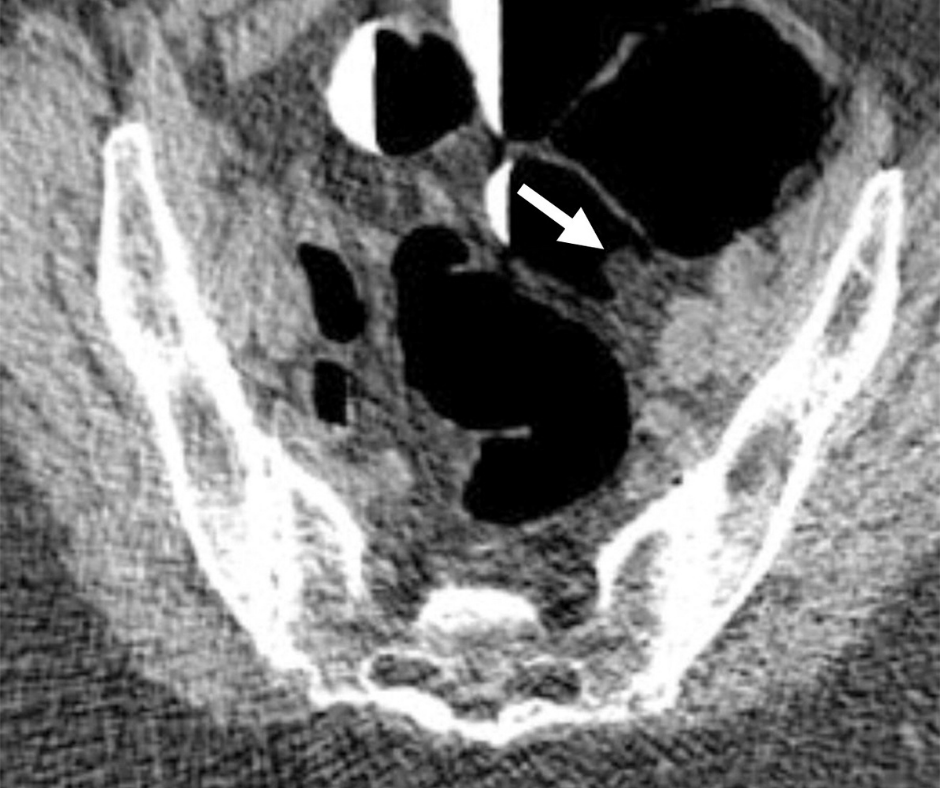

In a video interview earlier this year, Syam Reddy, MD, clinical president of the Ingalls Memorial Hospital of Medicine in UChicago, noted that CT colonography has better rates of cancer and precancerous lesions than others. noninvasive tests such as stool tests. and is comparable to the detection rates of conventional colonoscopy.

At a conference at the Society of Abdominal Radiology (SAR) meeting earlier this year, Dr. Reddy cited a study by researchers who found that preoperative CTC changed surgical management in more than 20 percent of patients who had occlusive colorectal cancer.